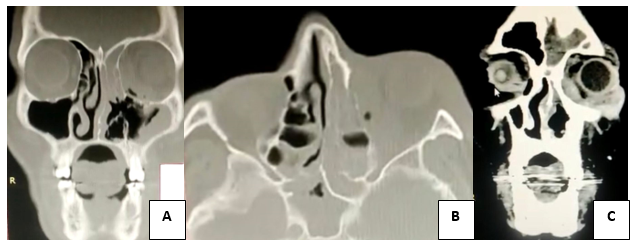

Se trata de un estudio prospectivo, comparativo, longitudinal realizado en 14 pacientes con diagnóstico de hipertrofia adenoidea (mediante radiografía lateral de cráneo con boca abierta), a los cuales se les realizó adenoidectomía, se realizó en el periodo de Enero a Junio del 2023, todos intervenidos por el mismo equipo de cirujanos del servicio de Otorrinolaringología y Cirugía de Cabeza y Cuello del Hospital Regional Dr. Valentín Gómez Farías del ISSSTE. Los criterios de inclusión fueron: pacientes derechohabientes, con historia clínica completa, que aceptaran firmar el consentimiento informado voluntariamente, pacientes entre 3 y 6 años de edad; con síntomas obstructivos y diagnóstico de hipertrofia adenoidea, valorados con el cuestionario de la Universidad de Stanford, con o sin retraso en el desarrollo del lenguaje, programados para adenoidectomía con o sin colocación de tubos de ventilación, en el periodo de Enero 2023 a Julio 2023. Los criterios de exclusión fueron: pacientes mayores de 6 años, Otros trastornos del neurodesarrollo: TEA, TDAH, discapacidad intelectual, retraso global del desarrollo, trastorno específico del aprendizaje.

i1.png

Se incluyeron 14 pacientes para este estudio, 2 del género femenino y 12 del género masculino, con un rango de edad de 3 a 6 años con una media de 5 años, dichos pacientes presentaban obstrucción de la vía aérea 40 al 90% corroborada por medio de radiografía, con un promedio de 69.3%; todos los pacientes contaban con timpanograma el cual reportaba 9 pacientes con curvas tipo B (61.5%) y 5 pacientes con curvas tipo A (38.4%). De los 14 pacientes 5 (30.7%) presentaban datos indirectos de hipoacusia prequirúrgicos. Se realizó adenoidectomía a los 14 pacientes, a 2 se les colocaron tubos de ventilación.